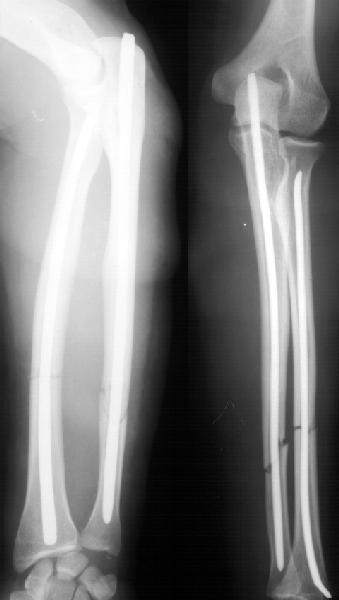

А зачем же неправильный гвоздь использовать, который нарушает? Наоборот, с помощью гводя нарушенная форма костей очень даже эффективно восстанавливается (см. пример). А неправильный

остеосинтез можно сделать чем угодно.

>Наоборот, с помощью гводя нарушенная форма костей очень даже эффективно восстанавливается (см. пример).

форма восстанавливается, но достаточной стабильности при таком остеосинтезе (пример) достигнуть трудно, ранние движения невозможны, а несращения встречаются как и при любом виде остеосинтеза.

А движения как раз начинаются максимально рано, на следующий день, включая ротацию - больших ран ведь нет, сильно не болит - в приложении картина в день снятия швов.

Так что стабильность достаточная. А то, что она не абсолютная, как с пластинкой - это как раз способствует периостальному сращению. Конечно, при многооскольчатых переломах для осевой устойчивости лучше запирать винтами.